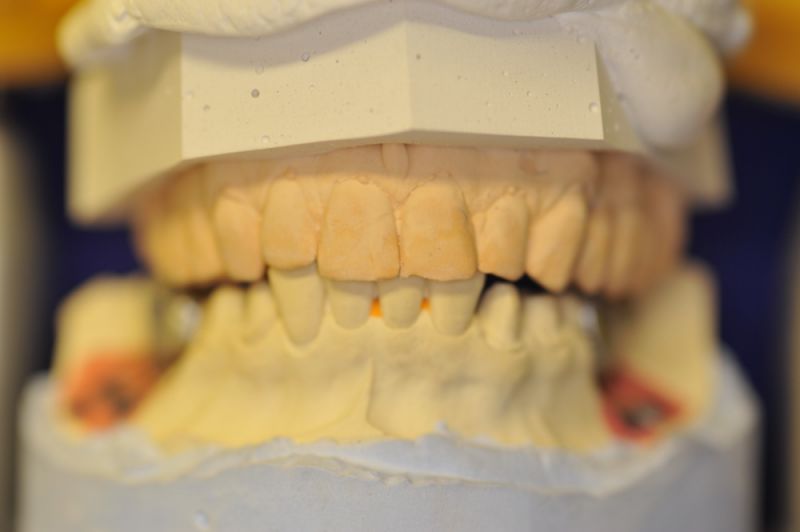

Neuromuskulär zentrierte Bisslage. Gerüste werden unbelastet durch das "Zahnfleisch" nach oben gehoben

Heute war nun Gerüsteinprobe, mit all den Problemen der Umsetzung zwischen Laborsituation und Mundsituation. Siehe Stichpunkt "Schnittstellenproblematik"! was bei Zähnen, auf Grund deren Eigenbeweglichkeit im Kieferkochen kein Problem wäre, ist bei drei unbeweglichen Implantaten ein Riesenproblem. Darüber spricht nur in aller Regel Niemand! Es musste viel fein nachgearbeitet werden.

4 Stunden haben wir heute Temporäre Aufbauten und provisorische Kronen entfernt. Definitive Aufbauten im Munde eingeschraubt. Eine erneute Bissregistrierung durchgeführt und die Arbeit neu artikuliert. Neue Provisorien mussten auch wieder hergestellt werden.